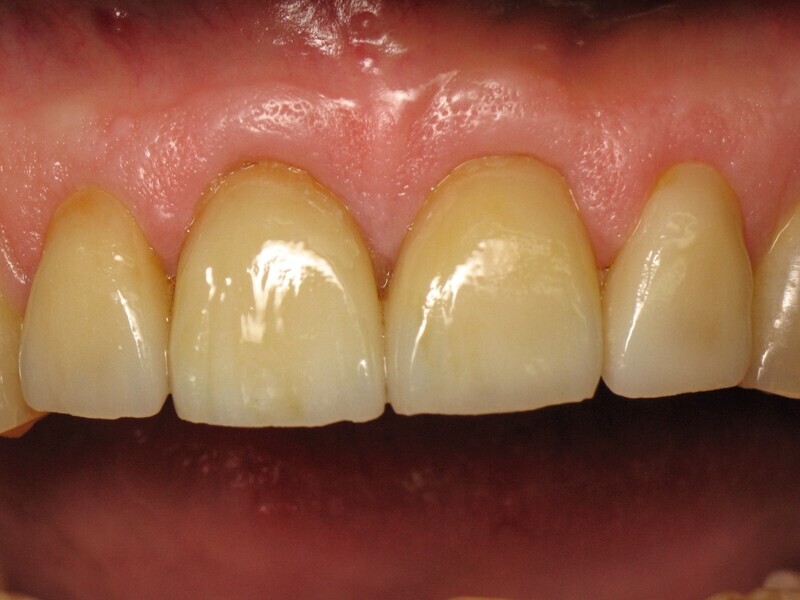

La figure 1 montre une situation clinique où le patient va pouvoir reprendre sa vie d’avant, avec le sourire au sens propre et au sens figuré. Les dents ont une forme, une position et une teinte harmonieuse, malgré des défauts mineurs, comme les lésions cervicales des incisives mandibulaires. La sante parodontale est également présenté avec l’absence de plaque ou d’inflammation gingivale. Ce que le lecteur est loin de se douter c’est que cette situation finale correspond à la pose de quatre couronnes sur les dents 12,11, 21 et 22.

Fig. 1: Situation finale.

Fig. 2 : Vue rapprochée de la situation finale.

La figure 2 nous montre en gros plan la qualité des restaurations et l’attention apportée par le prothésiste dentaire, dans la réalisation de ces couronnes. En effet, l’anatomie est harmonieuse et ne laisse aucun triangle noir au niveau des papilles gingivales. De plus, la teinte est naturelle avec une saturation progressive depuis le bord libre vers la région cervicale. Le technicien de laboratoire a ajouté une touche subtile de maquillant ocre en traits verticaux. Une attention toute particulière a été portée à ce cas clinique, pour un résultat qui dépasse les attentes du patient.